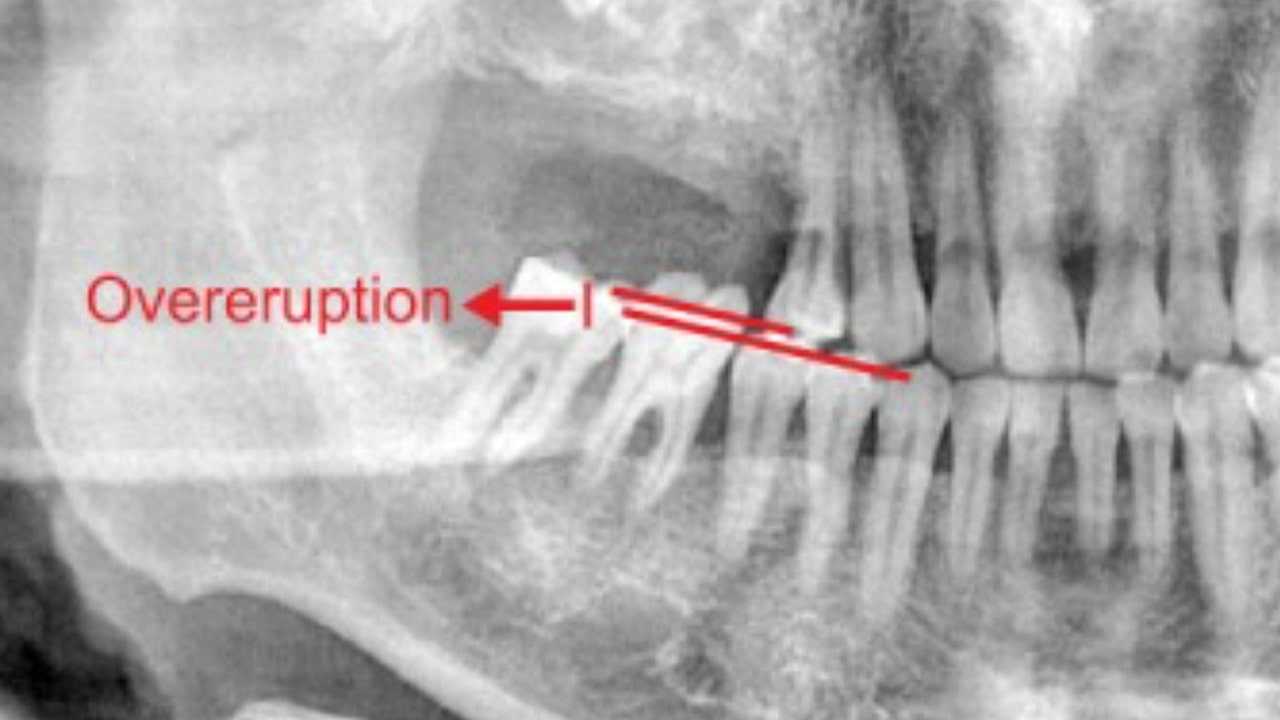

Discover the causes of super eruption and its impact on dental health. Learn effective solutions to protect your smile. Read more to stay informed!